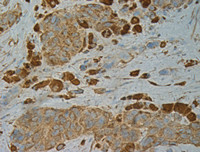

Immunohistochemistry:

B-Raf(V600E) monoclonal antibody (货号 26039). Tissue samples were fixed with formaldehyde and blocked with 1% serum for 15 min at 37 °C. Antigen retrieval was by heat mediation in citrate buffer (pH6). Samples were then incubated with primary antibody (1:100) overnight at 4°C. A HRP-conjugated Goat mouse IgG (dilution 1:50) was used as secondary antibody.

Immunohistochemical analysis of paraffin-embedded Thyroid Carcinoma tissue -with BRaf (V600E) monoclonal antibody (货号 26039). Tissue samples were fixed with paraffin. Samples were then incubated with primary antibody (1:100) overnight at 4°C. An HRP-conjugated Goat mouse IgG (dilution 1:50) was used as the secondary antibody. Allele-specific PCR validated to be Negative for BRAF V600E.

Immunohistochemical analysis of paraffin-embedded Thyroid Carcinoma tissue -with anti BRaf(V600E) monoclonal antibody (货号 26039). Tissue samples were fixed with paraffin. Samples were then incubated with primary antibody (1:100) overnight at 4°C.A HRP-conjugated Goat mouse IgG (dilution 1:50) was used as secondary antibody.Allele specific PCR validated to be Negative for BRAF V600E.